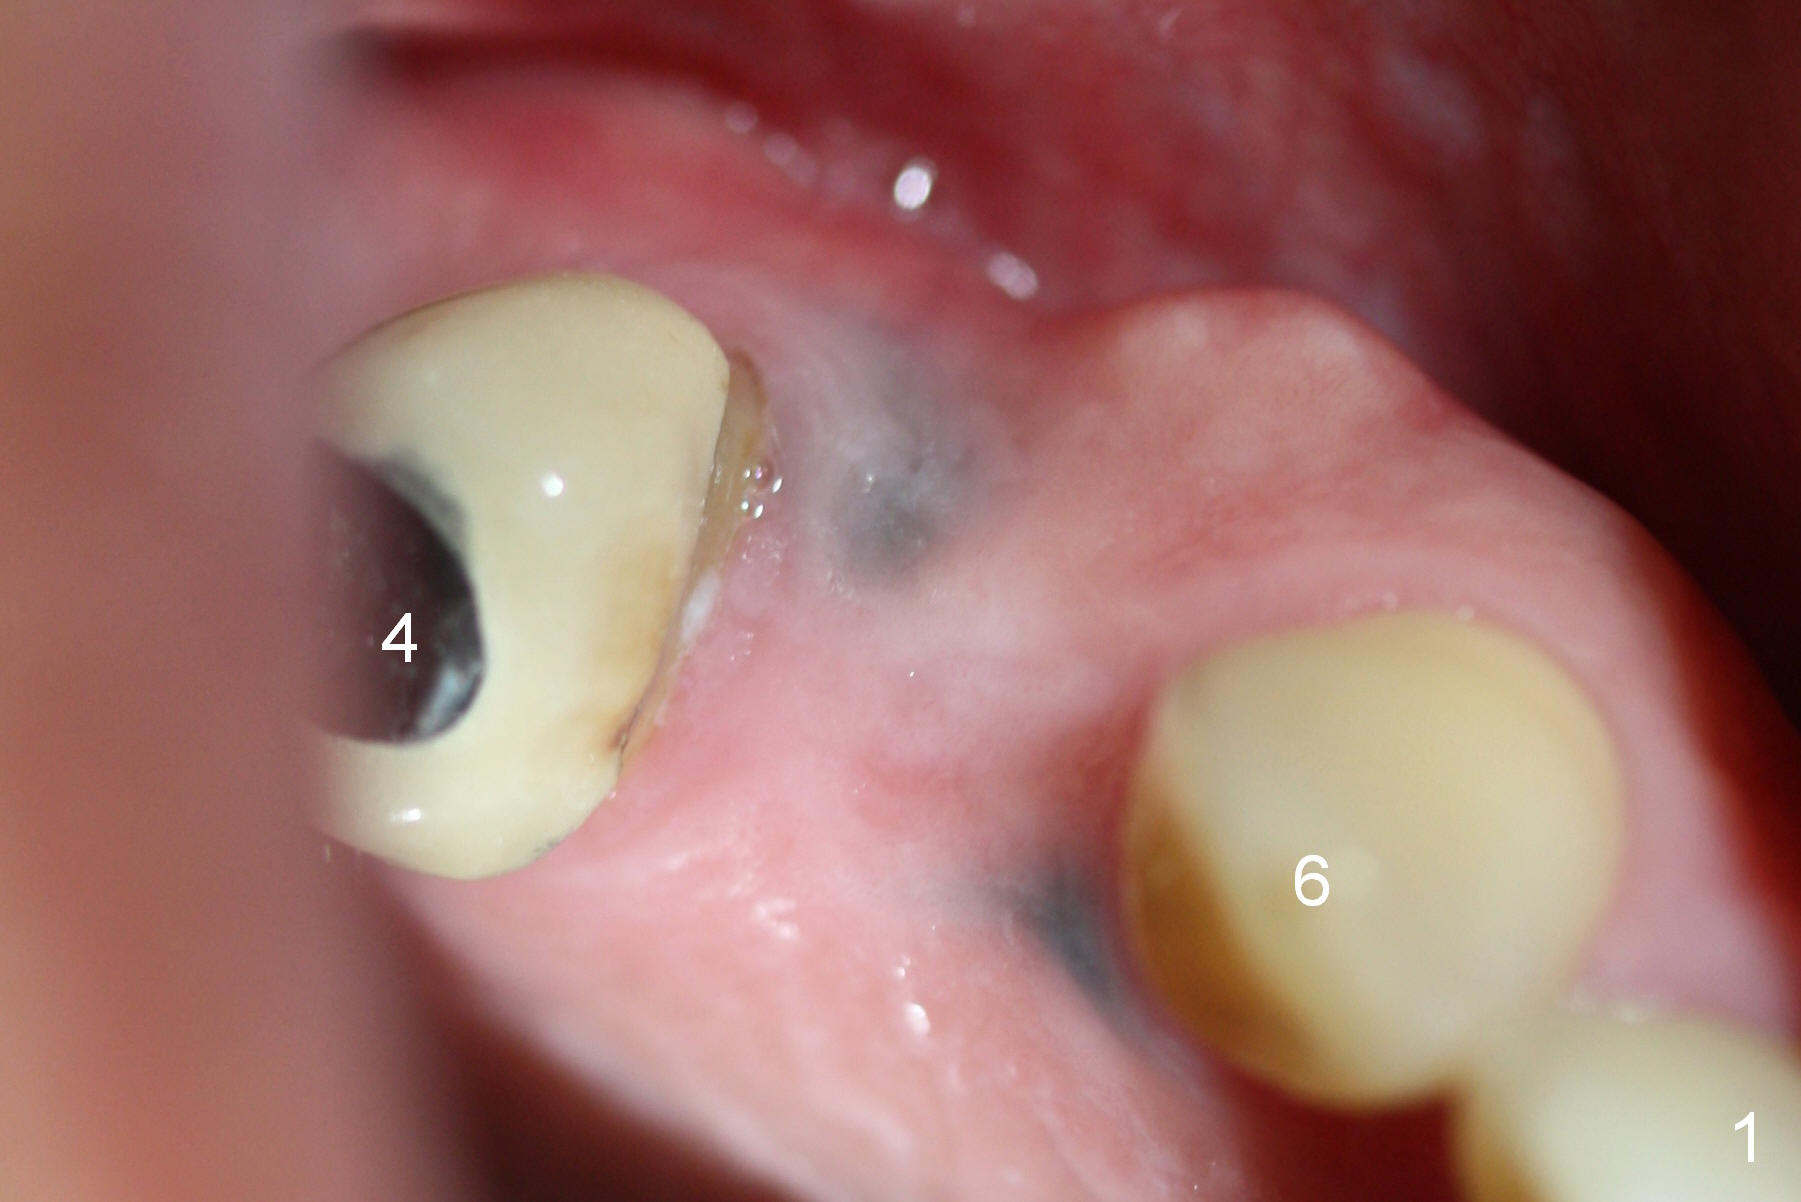

A 66-year-old man has lost several teeth (Fig.1,2). There is a particularly wide mesiodistal space for the site of #5 (Fig.1), probably due to distalization of the tooth #4 under heavy occlusion (Fig.2 arrow). A 4 mm tissue punch is used for access, followed by 1.6 mm pilot drill (Fig.3). After trajectory adjustment, a 2 mm parallel pin is inserted (Fig.4); later the osteotomy is moved distally (arrow). Finally a 4.5x14 mm implant is placed (Fig.5 I). Due to limited access, the implant is placed a little deeper than necessary; the gingival cuff of an abutment has to be longer (Fig.6 A: 5.8x4(3) mm). An immediate provisional is fabricated (Fig.7,8 P). The provisional looks wide (Fig.7). When the implant osteointegrates, limited orthodontic treatment will be done to idealize the space of #5 as follows.